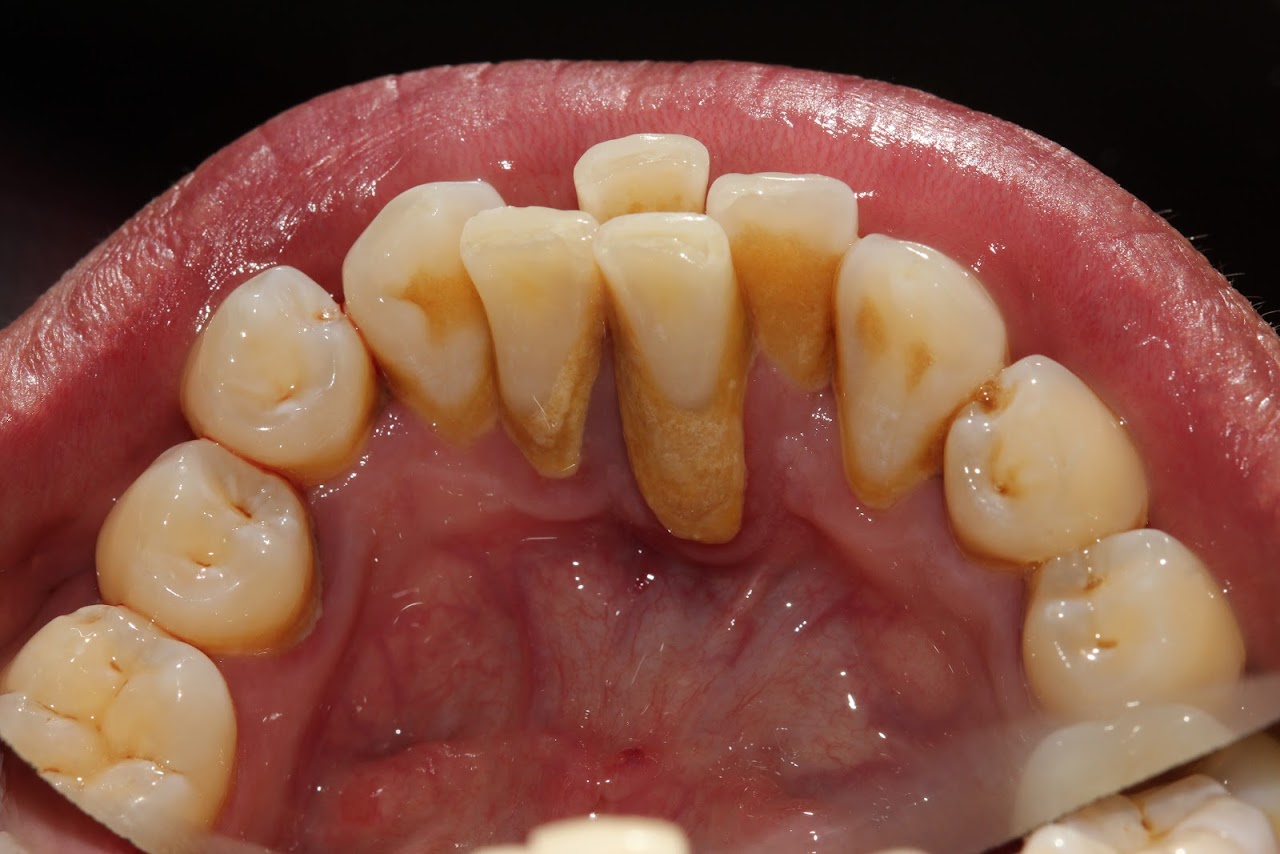

Sarro dental antes de limpieza

Eliminación con ultrasonido reduce la inflamación gingival. El sarro se forma a partir de residuos de alimentos + bacterias